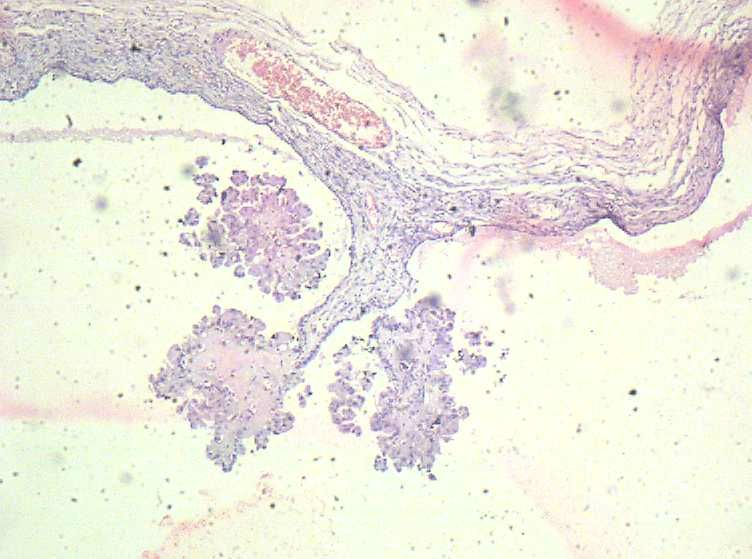

女,27岁,剖宫产术中见一侧卵巢一肿物。大体:椭圆形肿物大小3*2*1.5表面光滑,剖开内容为浅黄色胶状物,质均,囊内壁较光滑,部分见细小乳结构。

交界性浆液性乳头状囊腺瘤。瘤细胞的极向有紊乱。图8似有浸润。应考虑灶性癌变。

卵巢交界性浆液性乳头状囊腺瘤,似有微小浸润,不除外癌变

这是一个非常好的问题,妊娠合并交界性肿瘤是比较少见的,但确实遇到过几例。有限的经验显示:妊娠时确实会对瘤细胞产生影响,使得细胞增殖更旺盛,胞浆也显得丰富,甚至空亮,给人感觉异型性增大了。所以遇到妊娠时的卵巢上皮性肿瘤,应注意不要过诊断。判断细胞异型性要稍稍退一步。

有的文献讲,妊娠时交界瘤更容易出现微浸润。但是妊娠时判断“微浸润”的门槛是否应该提一提,这仍然有待积累病例进一步观察。曾经遇到过一例妊娠时交界性肿瘤,细胞生长非常旺盛,局部疑有微浸润。一年后,复发性肿瘤显示良性的浆液性囊腺瘤,连交界都够不上。